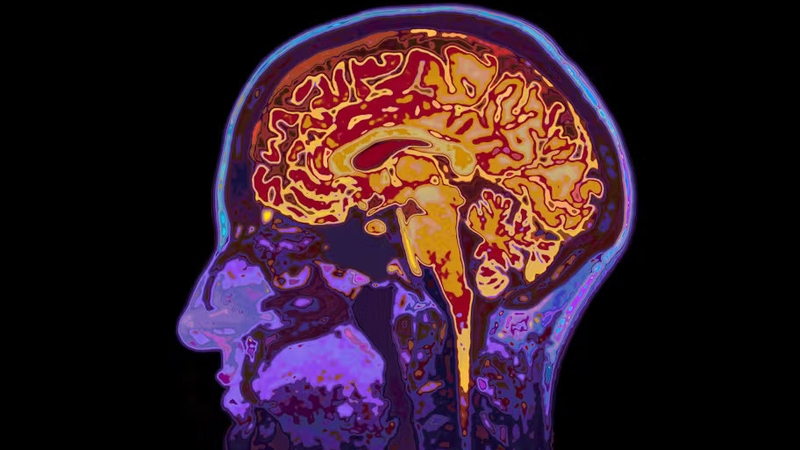

Our brain is the most complex organ in the body. Not only does it control basic life functions like breathing, organ function, and movement, it's also behind more complex processes – everything from thought, controlling our behaviour and emotions, and creating memories. But despite how important our brains are, many people still know very little about it. This is your brain, explained.

Even when we're sleeping, our brain is always active. It has to be to keep us alive. But different parts of the brain are responsible for different functions. The brain is divided into four pairs of lobes on each side of the head. The frontal lobes are located near the front of the head and the temporal lobes are just beneath them. The parietal lobes are located in the middle and the occipital lobes are at the back of the head.

The frontal lobe is often associated with what "makes us human". It's involved in cognitive processes such as reasoning, learning, creativity, attention and controlling muscles used for movement and speech. It also helps us make memories, and learn to regulate emotions and behaviour.

The parietal lobes are involved in a mixture of functions. These include sensory and numerical processing, as well as visuo-spatial information – which is needed for movement, depth perception, and navigation. The temporal lobes also receive information relating to sounds – including the language we hear – as well as in memory processes. The occipital lobes are involved in visual processing. When light enters your eyes, it's transmitted by nerves to this region and converted to an image that you "see".

The lobes are further divided into functional regions. These are individual regions of a certain lobe that's responsible for specific functions. For example, an area in the frontal lobe called Broca's area is specifically involved in language production and comprehension.

By scanning the brain, scientists can measure when and which areas become more active in the brain by looking at which areas experience an increase in blood flow, which delivers the extra oxygen the area needs to function or perform a task. Knowing which parts perform which tasks is important both for research, and when performing surgery.